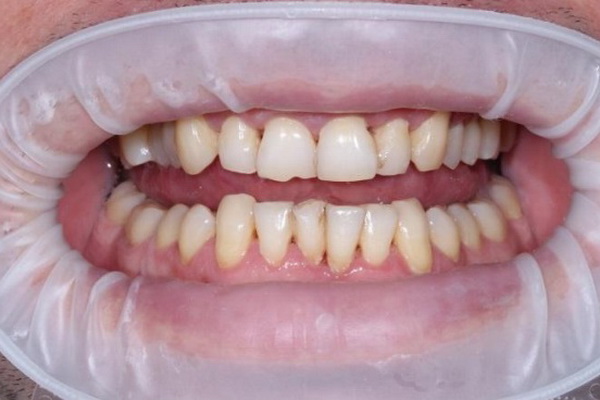

Стан ясен та зубів через 14 місяці після лікування (до та після проведення планової професійної гігієни ротової порожнини).

Не зважаючи на недостатньо якісну індивідуальну гігієну ротової порожнини ясна зберігають природній колір та незначно кровоточать при зондуванні.